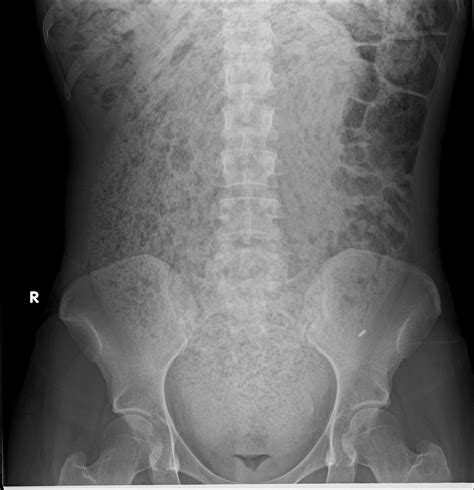

Interpreting Constipation in X-Ray

When interpreting an abdominal X-ray for constipation, radiologists look for several key indicators:

• Fecal Loading: The presence of a large amount of fecal matter in the colon.

• Colonic Dilatation: An enlarged colon, which may indicate chronic constipation.

• Air-Fluid Levels: The presence of air and fluid in the colon, which can suggest obstruction or slow transit.

These findings can help healthcare providers determine the severity of constipation and identify any underlying issues that may be contributing to the condition.